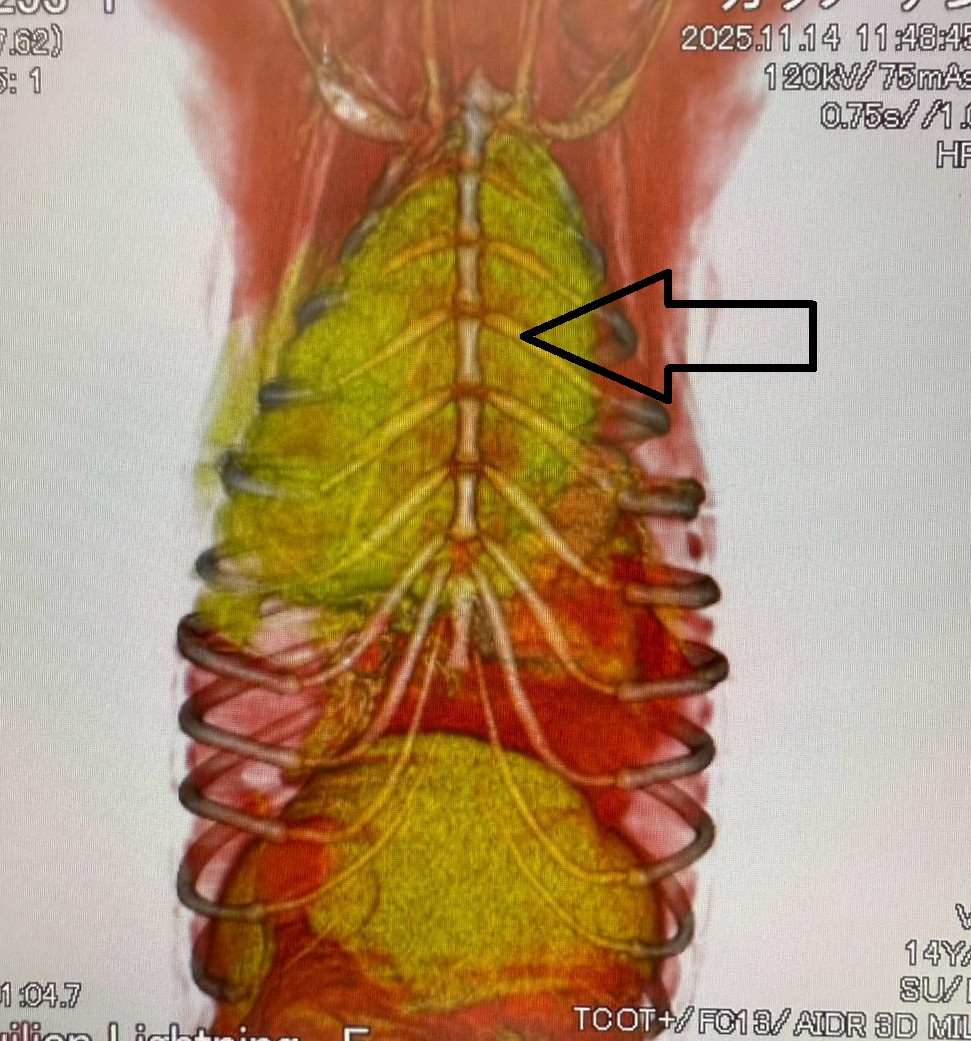

より詳しい評価が必要と判断し、沼津市の宮田動物病院にてCT検査をお願いしました。迅速に対応していただき、すぐにCT撮影を行っていただきました。

画像中の黒矢印で示した黄色の部分が、前胸部に認められた腫瘤です。

CT検査では、

- 前胸部腫瘤の大きさ

- 腫瘤に入り込む血管の走行

- 周囲臓器との位置関係

について、宮田先生からリアルタイムで非常に詳しく説明していただきました。